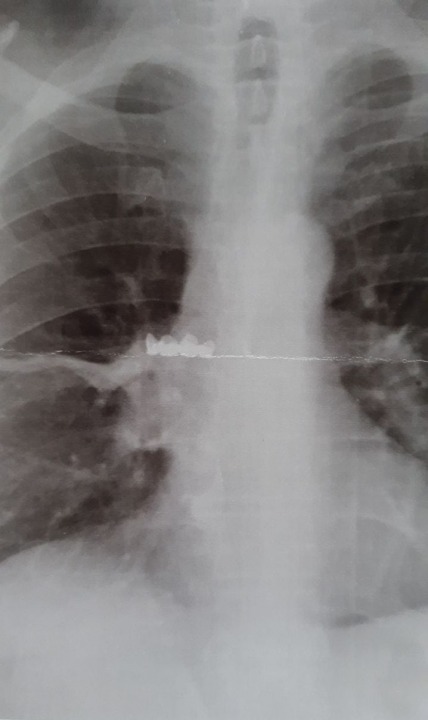

В детский эндоскопический центр обратился днепрянин с подозрением на коронавирус. Ему сделали рентгенограмму органов грудной клетки, во время которой обнаружили инородное тело в правом главном бронхе.

«На обзорной рентгенограмме органов брюшной полости инородного тела не было. В течении всего периода отмечался приступообразный кашель. С подозрением на COVID-19 была сделана рентгенограмма органов грудной клетки, где удалось найти, находившееся в правом главном бронхе, инородное тело. Выполнена фибробронхоскопии под местной анестезией с последующим его удалением », — написал в соцсетях врач-эндоскопист ДОДКБ Сергея Щудро.